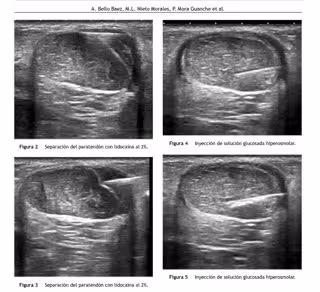

El tratamiento percutáneo de la tendinosis aquílea con proloterapia según el protocolo diseñado por el doctor Bello implica el uso de tres técnicas: hidrodisección del paratendón con lidocaína, punción seca de los focos de degeneración tendinosa (tendinosis) y por último la administración de solución irritante hiperosmolar a base de suero glucosado y anestesia dentro de los focos de tendinosis.